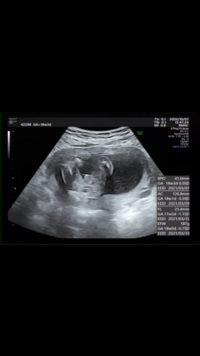

早くも妊娠5ヶ月で性別判明!?妊娠17週・18週のエコー写真 妊娠5ヶ月ごろだと、エコーでばっちりシンボルをみせてくれる男の子の赤ちゃんもいるようです。女の子とわかる場合もあります。 男の子のエコー写真妊娠17週 きぃさんのエコー写真18週の妊婦です(*˙ᵕ˙ *)よく、エコー中赤ちゃんが手足をパタパタ動かしてた~。などの投稿を見かけます( ᵒ̴̶̷̤⌔ᵒ̴̶̷̤ )が、私はいつも先生に寝ているね~と言われて心臓が動いているのしか見たことありません(;;)昨日のエコー中も寝ていたようで、先生がAug 07, 18 · 妊娠18週のエコー検査・赤ちゃんの様子や性別について 妊娠18週の赤ちゃんの様子は、身長が13~18センチ、体重は0グラム前後の大きさです。 さつまいもくらいのイメージだとわかりやすいでしょうか。

Nov 25, 18 · 妊娠18週には性器が完成しているので、赤ちゃんの体勢によっては性別の確認ができます。 妊娠5か月のお腹の赤ちゃんの成長をエコー写真とイラストで解説!この時期にしたいことSep 17, · 妊婦健診でもらう「エコー(超音波)」検査の写真をみると、愛おしい気持ちが高まりますね。ここでは、妊娠16週の赤ちゃんの特徴をイラストつきで解説するとともに、このころのエコー写真とママ達のエピソードを多数紹介します。Sep 18, · <妊娠18週の基準値> ・頭大横径(BPD):頭の最も大きい横幅396cm前後 ・腹囲(AC):お腹の周囲の長さ125cm前後 ・大腿骨長(FL):大腿骨の長さ253cm前後

Sep 17, · <妊娠18週の基準値> ・頭大横径(BPD):頭の最も大きい横幅396cm前後 ・腹囲(AC):お腹の周囲の長さ125cm前後 ・大腿骨長(FL):大腿骨の長さ253cm前後Sep 18, · 妊婦健診でもらう「エコー(超音波)」検査の写真をみると、愛おしい気持ちが高まりますね。ここでは、妊娠18週の赤ちゃんの特徴をイラストAug , 15 · 2回目:中期超音波検査(18~週くらい) 3回目:後期超音波検査(27~29週くらい) ※週数はあくまでも目安で、施設によって若干のばらつきがあります。 上記の細かい検査に加えて適宜赤ちゃんの成長を見るための超音波検査が追加されます。